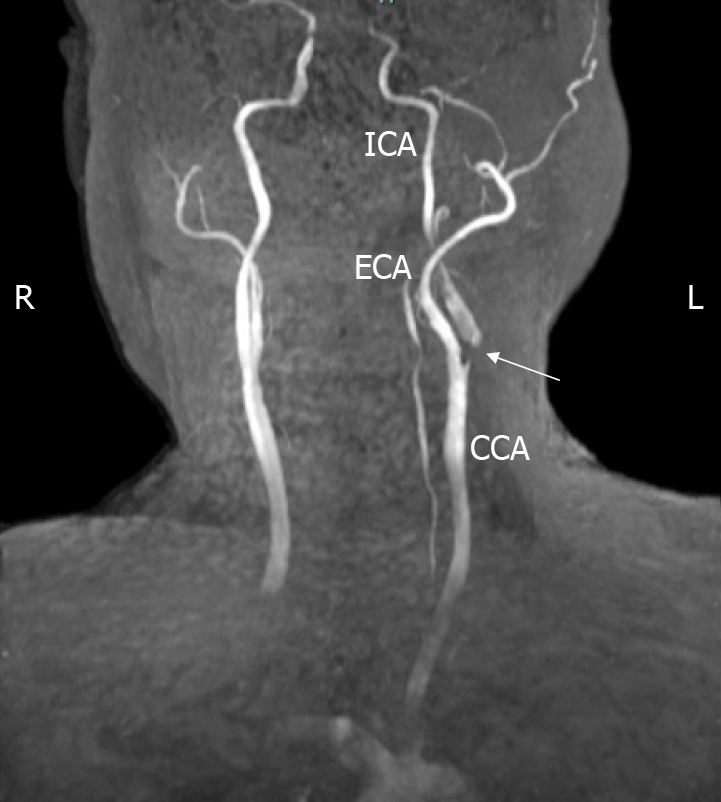

Figure 1 Magnetic resonance angiography.

Magnetic resonance angiography showing severe stenosis extending from the left common carotid artery to the bifurcation of the internal carotid artery. CCA: Common carotid artery; ICA: Internal carotid artery; ECA: External carotid artery; R: Right; L: Left.